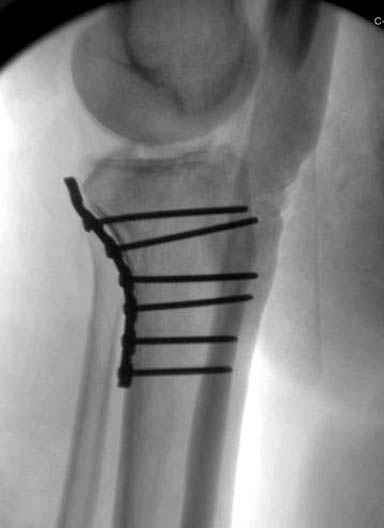

Уважаемые коллеги! В прошлую пятницу больной прооперирован - как и планировалось мыщелковая LCP от ChM. Малоинвазивно не получилось - один большой доступ :(. (но с минимальным скелетированием б/б кости). Наружный мыщелок собрали, но по контролю видно, что задне-медиальный отдел метаэпифиза смещен. Фиксировать не стали (?). 4-е сутки после операции - по м/тканям без проблем. Дополнительная иммобилизация синтетическим тутором.

Интересно услышать ваши мнения, анализ ошибок...

P. S. перелом диафиза на контроле не совсем захвачен, но проблем там нет. Приношу извинения за низкое качество Р-грамм - выполнены на сканере (фотоаппарат не работает :)) .

Трудно поверить, что разрекламированная Ортопедическая школа Восточной Украины позволяет такие странные снимки? На прямом снимке сохранен общий контур плато, но не известна судьба импрессии суставной поверхности. На полубоковой?, оставлен без репозиции задне-медиальный отдел, и навряд ли после такой фиксации можно удовлетвориться результатом.

Такая ситуация характерна для многих, когда принимается ошибочное решение, т.е пытаются фиксировать одним имплантом переломы двух мыщелков. Латеральная пластина приемлема только для тех случаев, когда сохраняется интактным медиальный диафизарный кортекс и отсутствует фрагментация на верхушке медиального перелома.